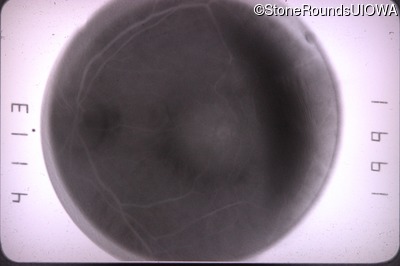

Fluorescein Angiography - Right - 20/70

Exemplar